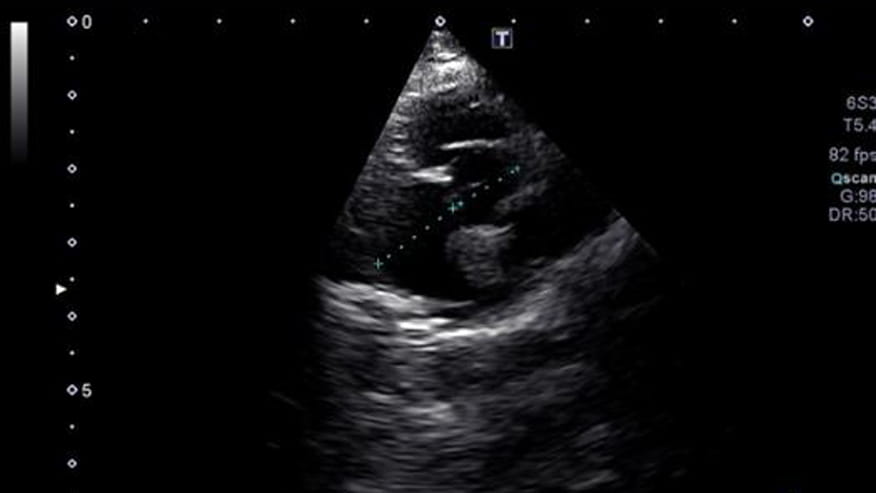

• 876x493 encina echocardiography

An echocardiogram is an ultrasound (sonogram) exam of the heart. Many times both radiographs (X-rays) and ultrasound of the heart are recommended for best evaluation of heart disease. X-rays show the size, shape and position of the heart and the ultrasound allows your veterinarian to see the internal structure and function of the heart.... Read more